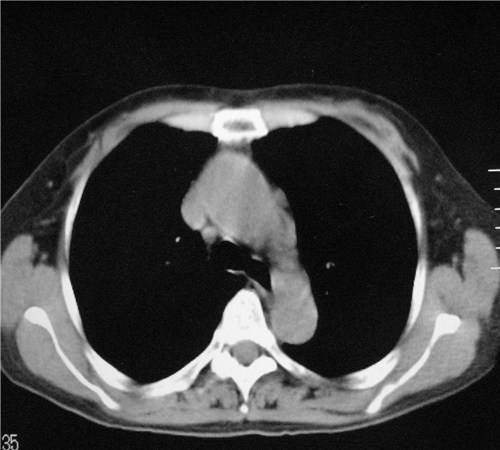

标题: CT26849:女67岁反复胸痛两天余,临床考虑夹层。 [打印本页]

标题: CT26849:女67岁反复胸痛两天余,临床考虑夹层。

右肺感染,未见夹层。

未见夹层

既然考虑夹层,建议强化!另:右下肺感染!

1)右肺感染性病变。2)建议行ct增强扫描或mri检查排除主动脉夹层。

双下肺感染,右侧显著。有无夹层,增强扫描后再诊断。

1. 感染性病变,2.未见夹层,3.食道未见异常。